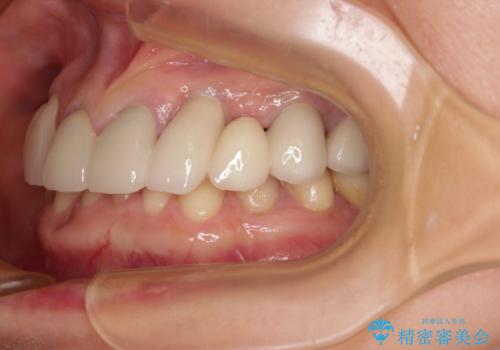

割れてしまった歯が痛む 矯正とインプラントを併用した総合歯科治療

- 割れていると言われて放置してしまった歯や、前歯のデコボコなどが気になるとのことで来院された患者様です。

左上の歯は割れてしまっており、抜歯のうえインプラント治療が必要であり、他にも抜歯の必要な歯がある状態でした。

上顎はほぼ全ての歯をセラミッククラウンにて補綴治療を行う必要があるため、気になるデコボコや深い咬み合わせを改善するために下顎と上顎の臼歯部の矯正治療を行うこととしました。

過蓋咬合(下顎前歯が隠れてしまうほどの深い咬み合わせ)のため、スムーズに歯が動かず矯正治療に時間がかかりましたが、無事に仕上げることができました。